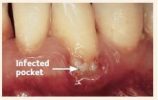

The following images show the progression of gum disease:

2. Infection due to plaque (germs) and calculus (tartar) beginning to destroy the supporting gums and bone around the teeth.

Once the bacteria work their way between your gums and your teeth, they become harder to remove.

Healed Site After Periodontal Surgery

Healed pocket after treatment.

If pockets do not heal enough after scaling and root planing, gum surgery may be needed.